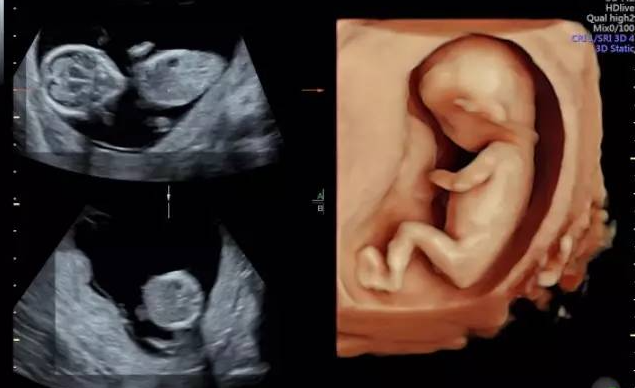

做四维彩超双胞胎为什么产检费用很贵?

简单来说,做一例双胞胎四维彩超,其工作量、技术难度、时间消耗和医生所承担的压力,···【详情】

温州孕妈们关于NT、四维彩超、小排畸检查,你了解多少?

温州孕妈们关于NT、四维彩超、小排畸检查,你了解多少?对于妈妈而言,宝宝的健康永···【详情】